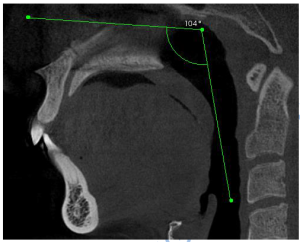

Her evaluation revealed:

- Mouth opening: 48 mm (adequate but painful)

- Bite: Well-aligned

- Muscle tenderness: Lateral pterygoid, masseter, temporalis

- MRI: Bilateral disc displacement without reduction

Instead of surgery, Aparna began customized orthotic therapy—a conservative, non-surgical approach designed for healing with care.